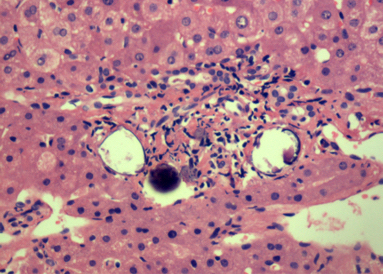

Microscopic (histologic) description

- Ova are mainly seen in the loose submucosa of large intestine, usually with formation of granulomas and infiltration by eosinophils and inflammatory cells

- Later the muscularis mucosa becomes involved and the overlying mucosa shows small superficial ulcers

- Fibrosis develops in chronic stage, when only calcified eggs are seen

Microscopic (histologic) images

Contributed by Nalini Bansal Gupta, M.D., Lisa Cerilli, M.D. and @zaalruwai83 on Twitter